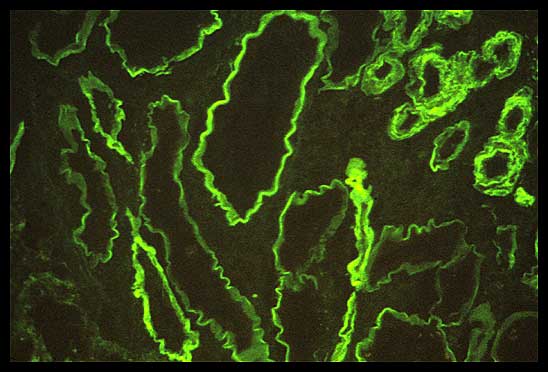

Immunofluorescence staining of non-amyloid MIDD

The diagnosis is made by the immunofluorescence. And it is interesting in that it is the tubules. What you see here is kappa fluorescing along the basement membrane of the tubules in these patients. In fact, one of the primary features is that the tubules will be positive for immunofluorescence for the monoclonal protein. Most commonly, it is light chains and again kappa more often. But people have described heavy chain deposition disease, as well as light and heavy chain deposition disease.

On immunofluorescence, these nodules, as well as Bowman's capsule, will light up with the monoclonal protein stain.